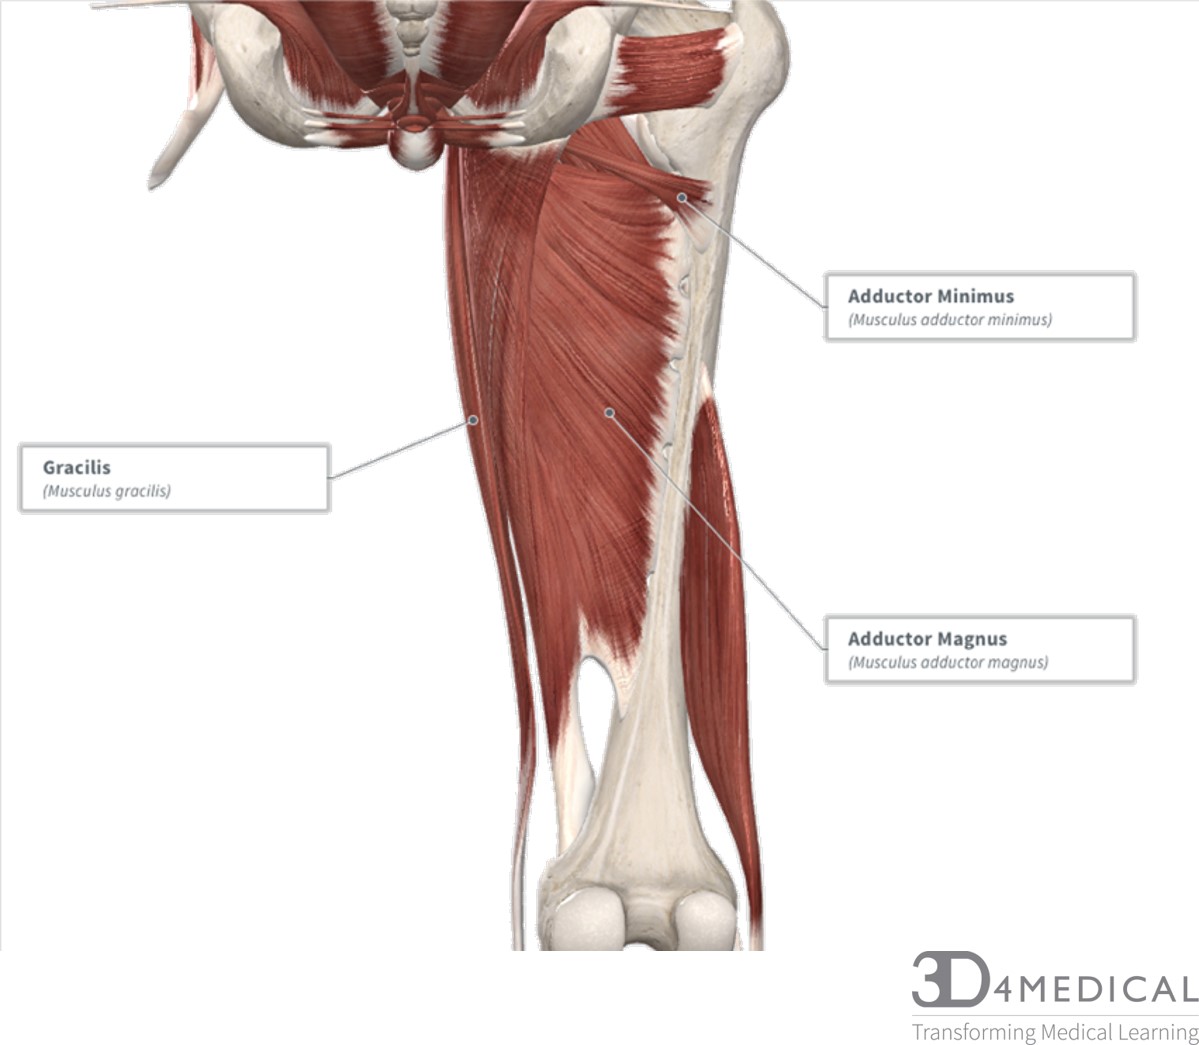

Анатомия и Функции Мышцы Adductor Magnus